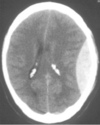

Label the figure.

- superior sagittal sinus

- inferior sagittal sinus

- straight sinus

- confluence of sinuses

- transverse sinus

- sigmoid sinus

- cavernous sinus

- intercavernous sinus

- posterior intercavernous sinus

- sphenoparietal sinus

- superior petrosal sinus

- inferior petrosal sinus